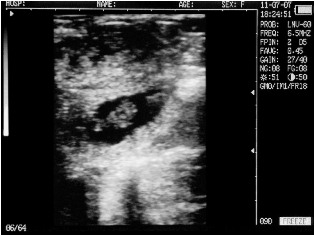

Cow with calf. Deadline - 30 days